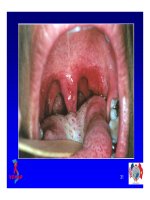

 Nấm miệng

 Lao

 Hội chứng suy kiệt

 Nhiễm trùng hô hấp

 Cryptococcus

 P. Marneffei

 PCP

 Nhiễm trùng máu

53%

37%

34%

13%

9%

7%

5%

4%